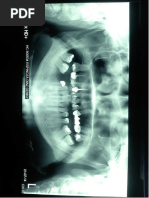

PUNTOS DENTARIOS ANATÓMICOS:  Incisivo central superior izquierdo  Incisivo central inferior derecho  Primer molar superior e inferior izquierdos .

y por los bordes incisales de los I  Eje del incisivo superior  Eje del incisivo inferior  Eje del primer molar maxilar  Eje del primer molar mandibular .PLANOS DENTARIOS:  Plano oclusal  Pasa por las cúspides de los M y PM.